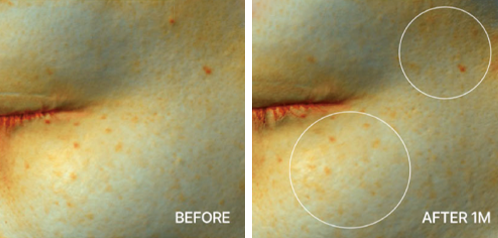

탄력 개선

탄력 개선